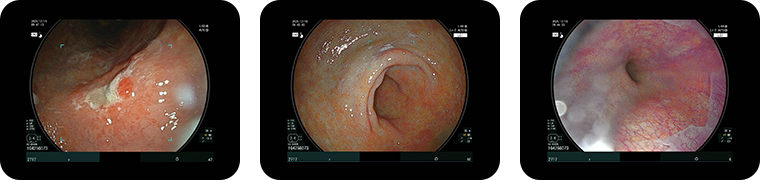

胃カメラ(上部消化管内視鏡検査)は、細いスコープを用いて食道 十二指腸 を直接観察する検査です。 炎症・潰瘍・ポリープ・出血・がんなどをその場で確認でき、必要に応じて組織検査(生検)も行います。当院では経鼻内視鏡にも対応しており、嘔吐反射が心配な方にも配慮しています。

内視鏡検査のエコー画像

• 内視鏡検査の様子